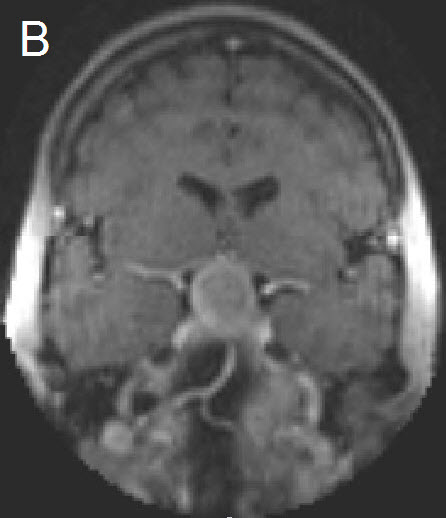

Figure 1 Illustrative case: Preoperative, intraoperative and postoperative imaging. A: Preoperative MRI, coronal view, contrast enhanced. B: Intraoperative MRI, coronal view, contrast enhanced, before skin incision. C: Intraoperative MRI, coronal view, contrast enhanced, during resection. D: Intraoperative MRI, coronal view, contrast enhanced, before closure. E: Postoperative MRI, coronal view, contrast enhanced.

A forty-two year old female was admitted for resection of a large pituitary adenoma. She complained about headache, amenorrhea and galactorrhea. Endocrinological diagnosis revealed a panhypopituitarism. The patient underwent surgery and the non-functioning pituitary adenoma could be totally removed. Postoperative follow-up showed normal pituitary function and the patient has now been in remission for 48 months. The figures show preoperative imaging, intraoperative imaging with various stages of the tumour resection, and postoperative follow-up MRI.